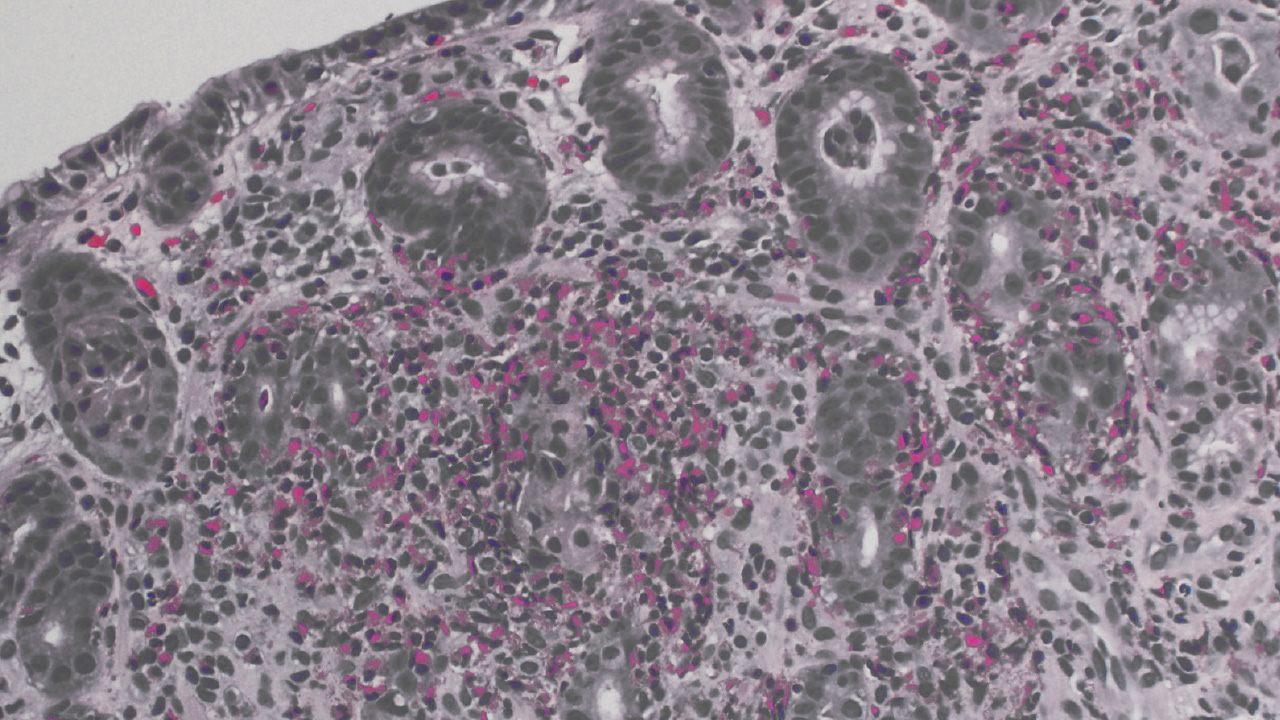

In the team’s research, published in the February 2024 issue of the American Journal of Gastroenterology, Dr. Quinn employed a broad array of International Classification of Diseases (ICD) codes to ensure a comprehensive capture of potential cases, followed by a meticulous manual review of patients’ charts to identify potential cases of EGIDs (1). This approach distinguished between EoG, EoD and low-grade tissue eosinophilia based on the location and intensity of eosinophil infiltration. Dr. Quinn described the patient identification process as uniquely rigorous, which ensured the integrity and reliability of their findings.

The revelation of increased diagnosis rates for eosinophilic gastritis and enteritis brought to light by Dr. Quinn and her team’s research marks a pivotal moment in the field of gastroenterology. It also underscores a potential shift in the epidemiological landscape of EGIDs by challenging the conventional understanding that the small intestine is more frequently implicated in EGIDs than the stomach, suggesting a broader spectrum of gastrointestinal involvement. This shift in understanding has the potential to inform more targeted and effective treatment approaches for EGIDs.